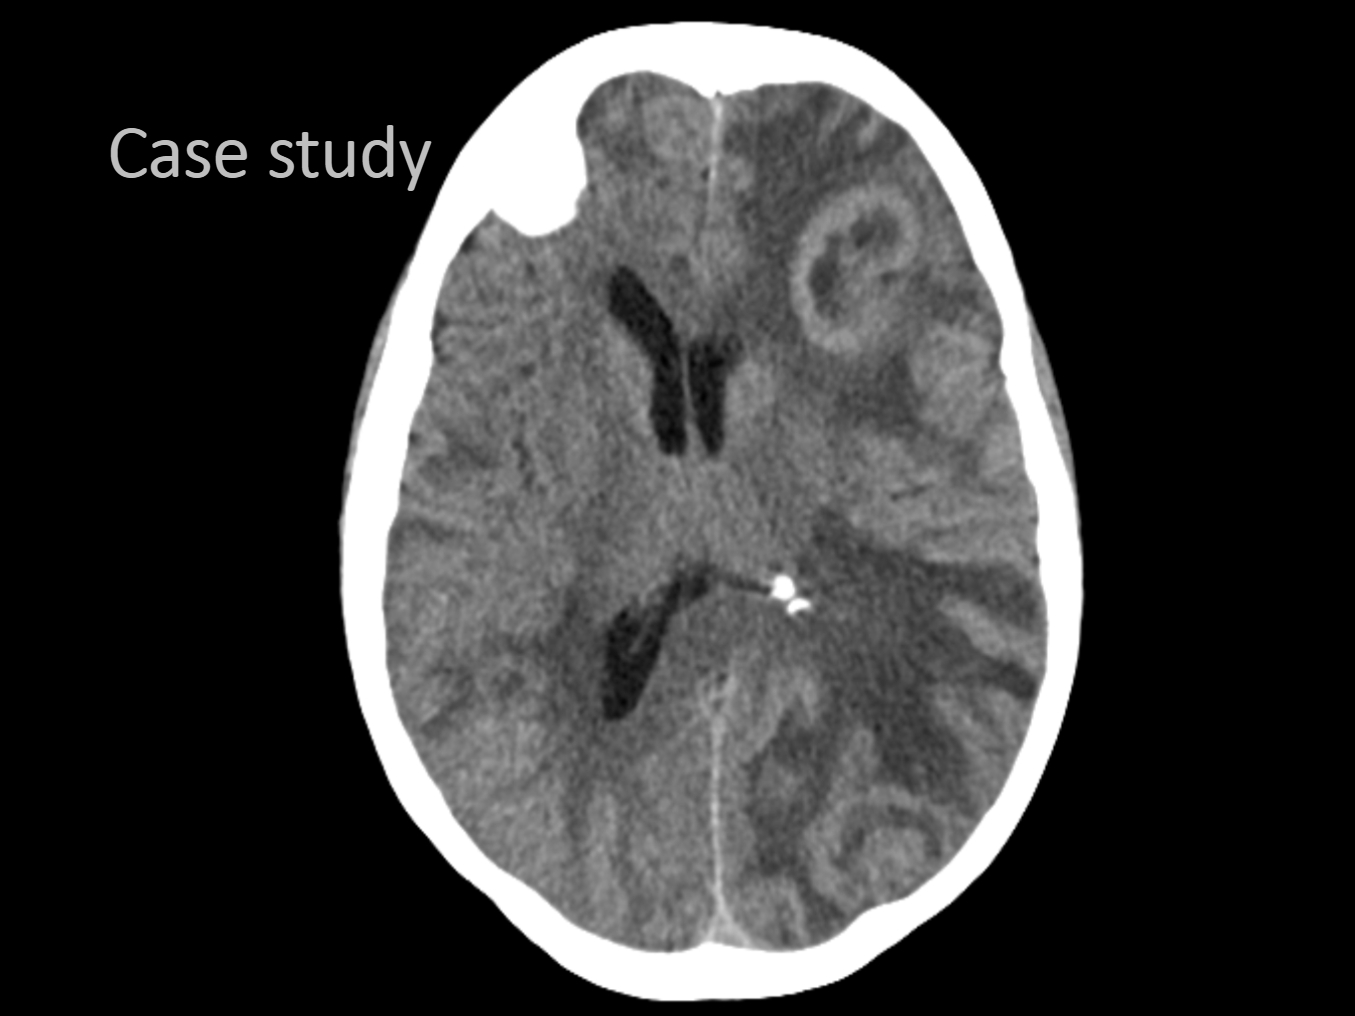

- CT scan comparisons

Part II allows the grads to ask Deigo questions regarding his experience and Ilsedora gives a ground breaking presentation comparing 5 different series of CT scans taken without contrast of a patient with multiple brain tumors.